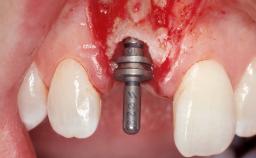

A 33-year-old female patient presented with an upper left central incisor that required extraction after a failed endodontic therapy. The tooth had been traumatized when the patient was a teenager and had undergone several endodontic treatments, including two apicectomy procedures. The patient was in good health and did not smoke. Clinical examination showed that the patient had a high lip line. In full smile, the gingival margins of the upper teeth were visible to the first molars. The gingival margins of central incisors 11 and 21 were only just showing. Examination of tooth 21 confirmed that the tooth was mobile and had hypererupted by 1 mm.

Placement Protocol Immediate implant placement

Tooth Site Maxillary incisor or canine

Socket Morphology Single-root socket

Socket Integrity Damage to one or more bone walls

Bone Volume Damage to one or more socket walls